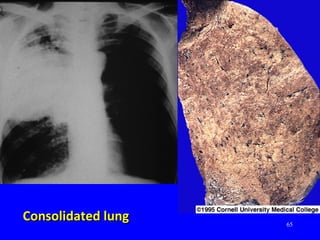

Consolidated lungConsolidated lung

57 Pneumococcal pneumoniaPneumococcal pneumonia Rupper lobe consolidation with Air BronchogramR upper lobe consolidation with Air Bronchogram